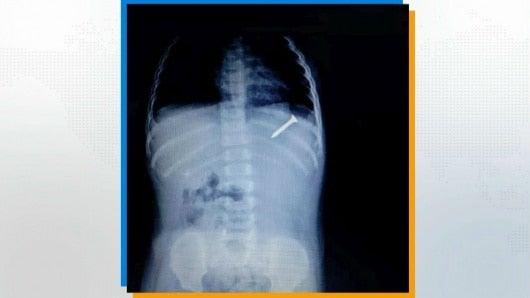

Bebé que accidentalmente se tragó un tornillo espera por cirugía urgente

El metal se ubica en un costado del pecho de la niña de 11 meses y amenaza con llegar a los pulmones.

La menor se comió el tornillo cuando su papá se encontraba reparando una motocicleta. De inmediato fue llevada de urgencias al hospital regional donde una radiografía deja ver que se trata de un tornillo de aproximadamente 5 centímetros.